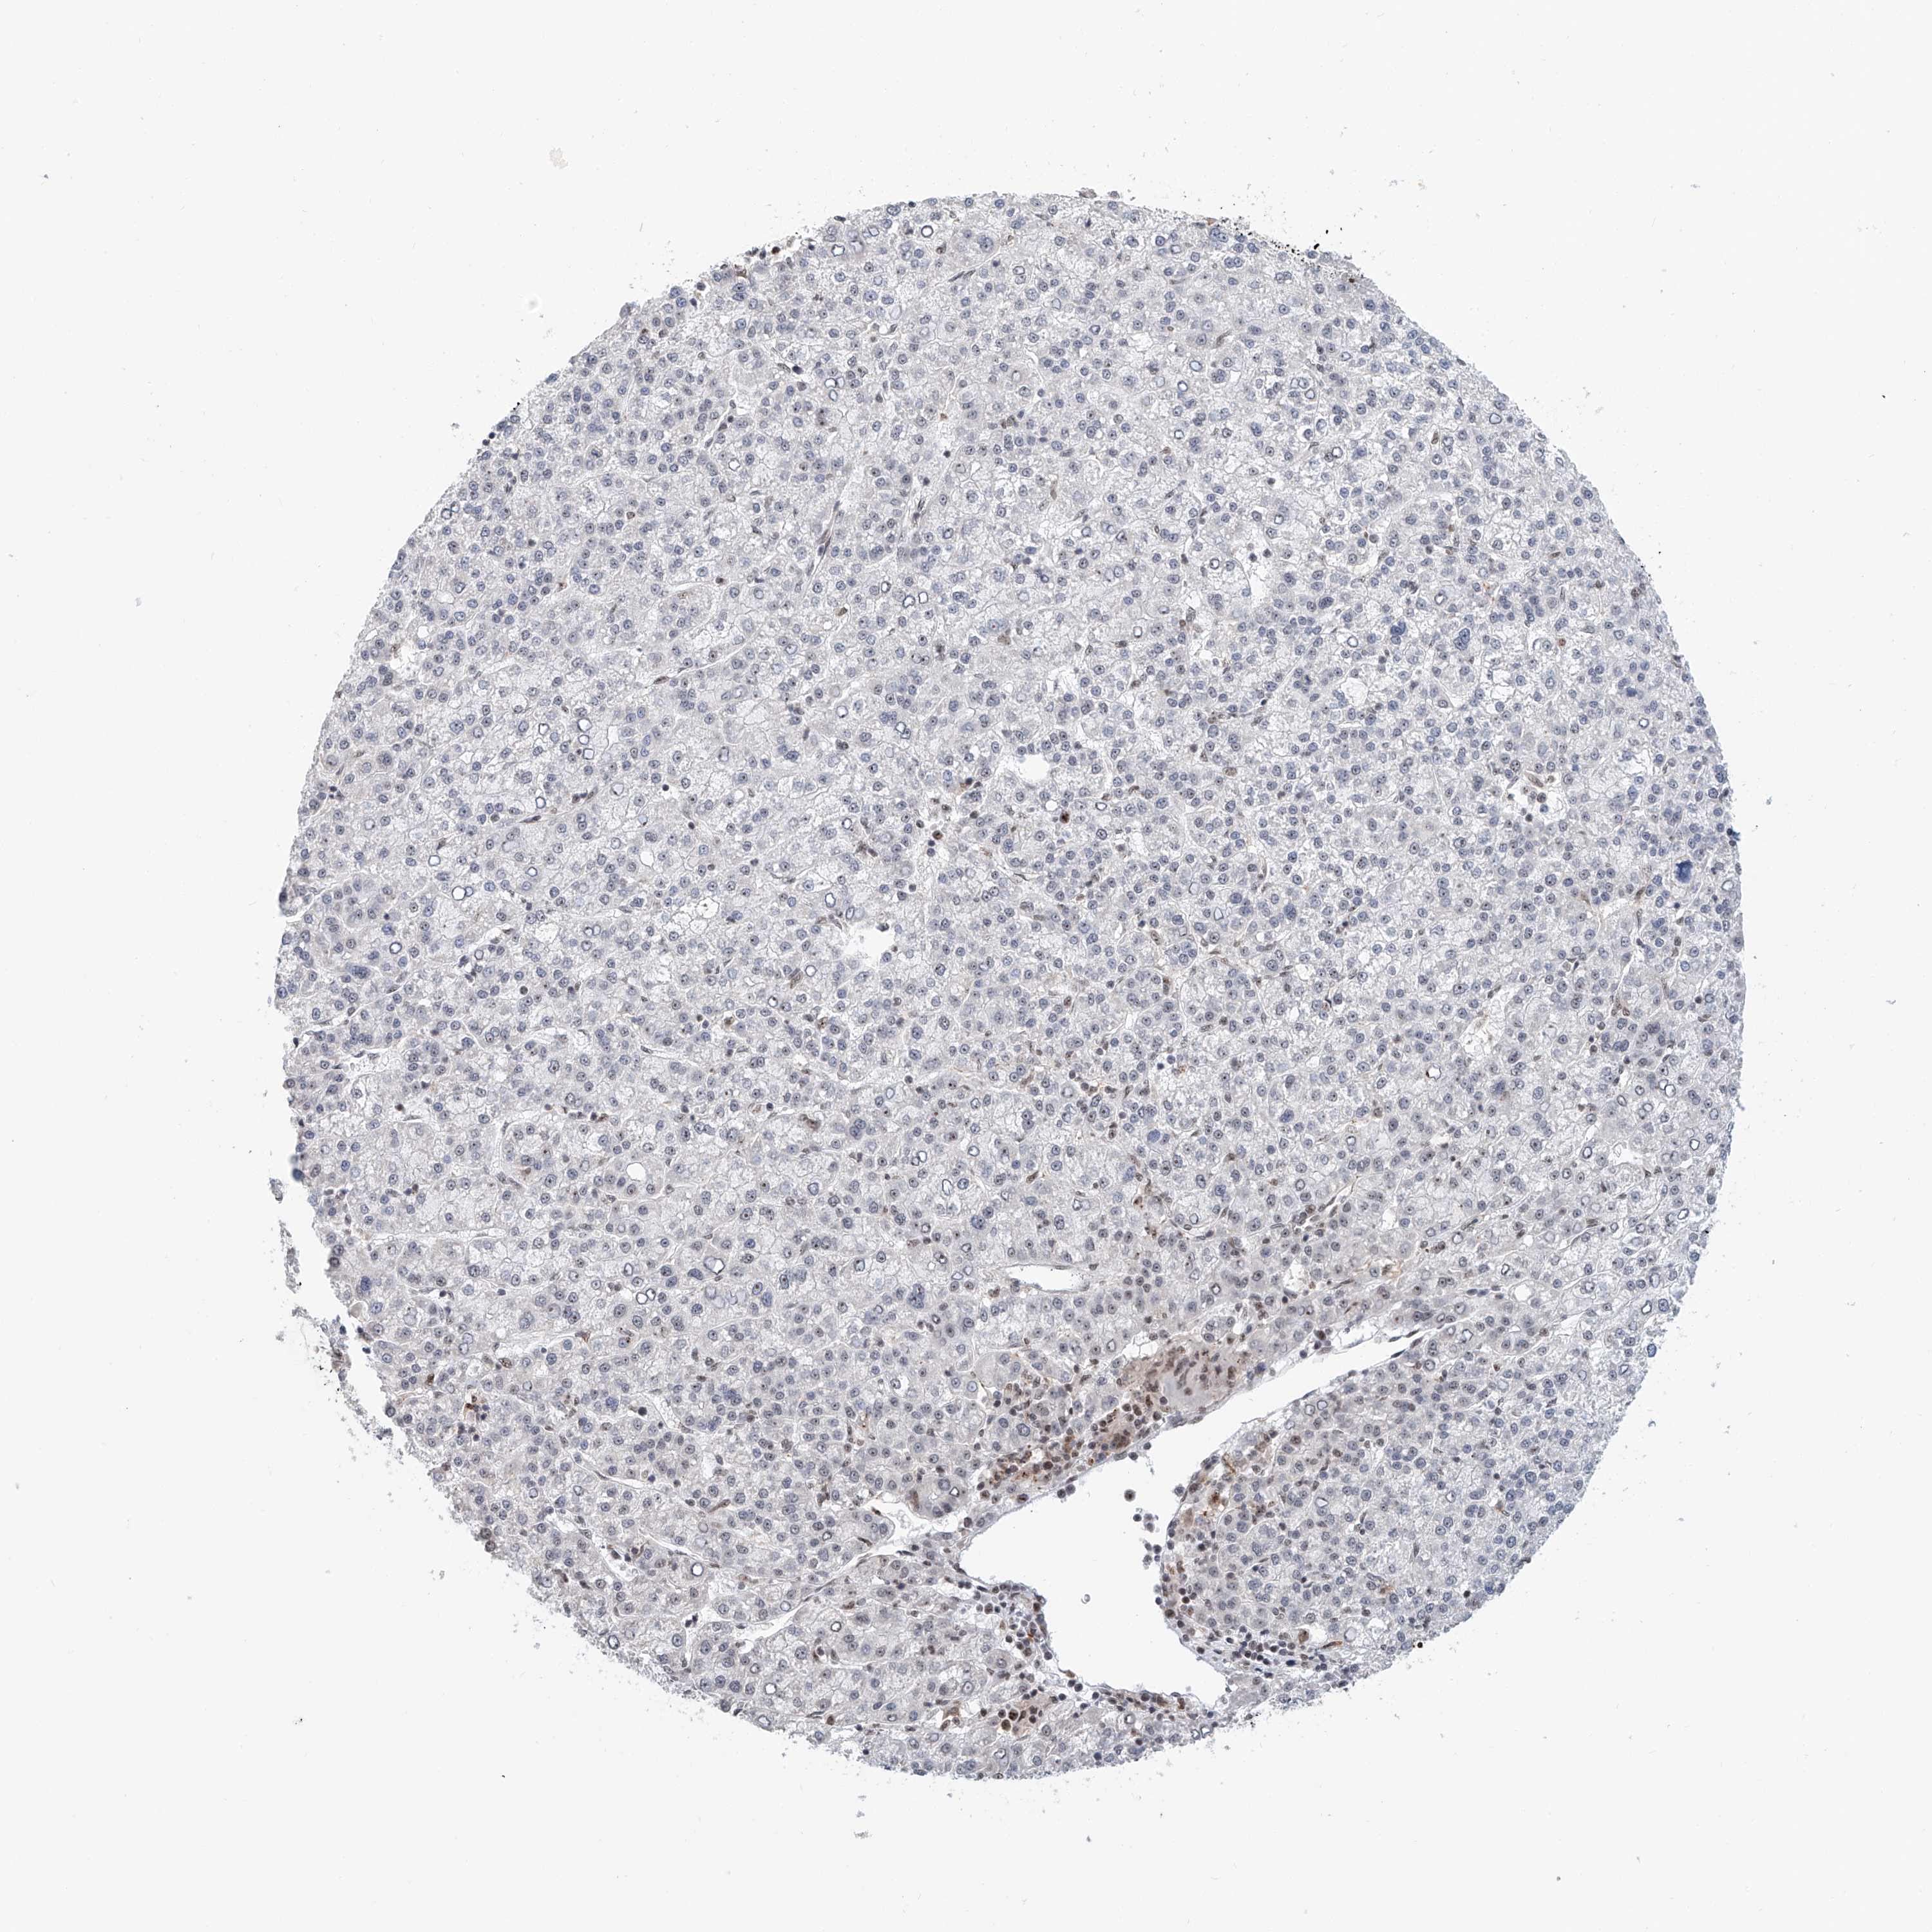

LIVER CANCER - Protein expressioni

A mouse-over function shows sample information and annotation data. Click on an image to view it in a full screen mode. Samples can be filtered based on level of antibody staining by selecting one or several of the following categories: high, medium, low and not detected. The assay and annotation is described here.

Note that samples used for immunohistochemistry by the Human Protein Atlas do not correspond to samples in the TCGA dataset.

Antibody stainingi

Antibody staining in the annotated cell types in the current human tissue is reported as not detected, low, medium, or high, based on conventional immunohistochemistry profiling in selected tissues. This score is based on the combination of the staining intensity and fraction of stained cells.

Each image is clickable and will lead to virtual microscopy that enables deeper exploration of all samples and also displays staining intensity scores, fraction scores and subcellular localization as well as patient and tissue information for each sample.

Antibody HPA022470

Antibody HPA031079

Staining

High

Medium

Low

Not detected

Intensity

Strong

Moderate

Weak

Negative

Quantity

>75%

75%-25%

<25%

None

Location

Nuclear

Cytoplasmic/membranous

Cytoplasmic/membranous,nuclear

Cholangiocarcinoma

Carcinoma, Hepatocellular, NOS